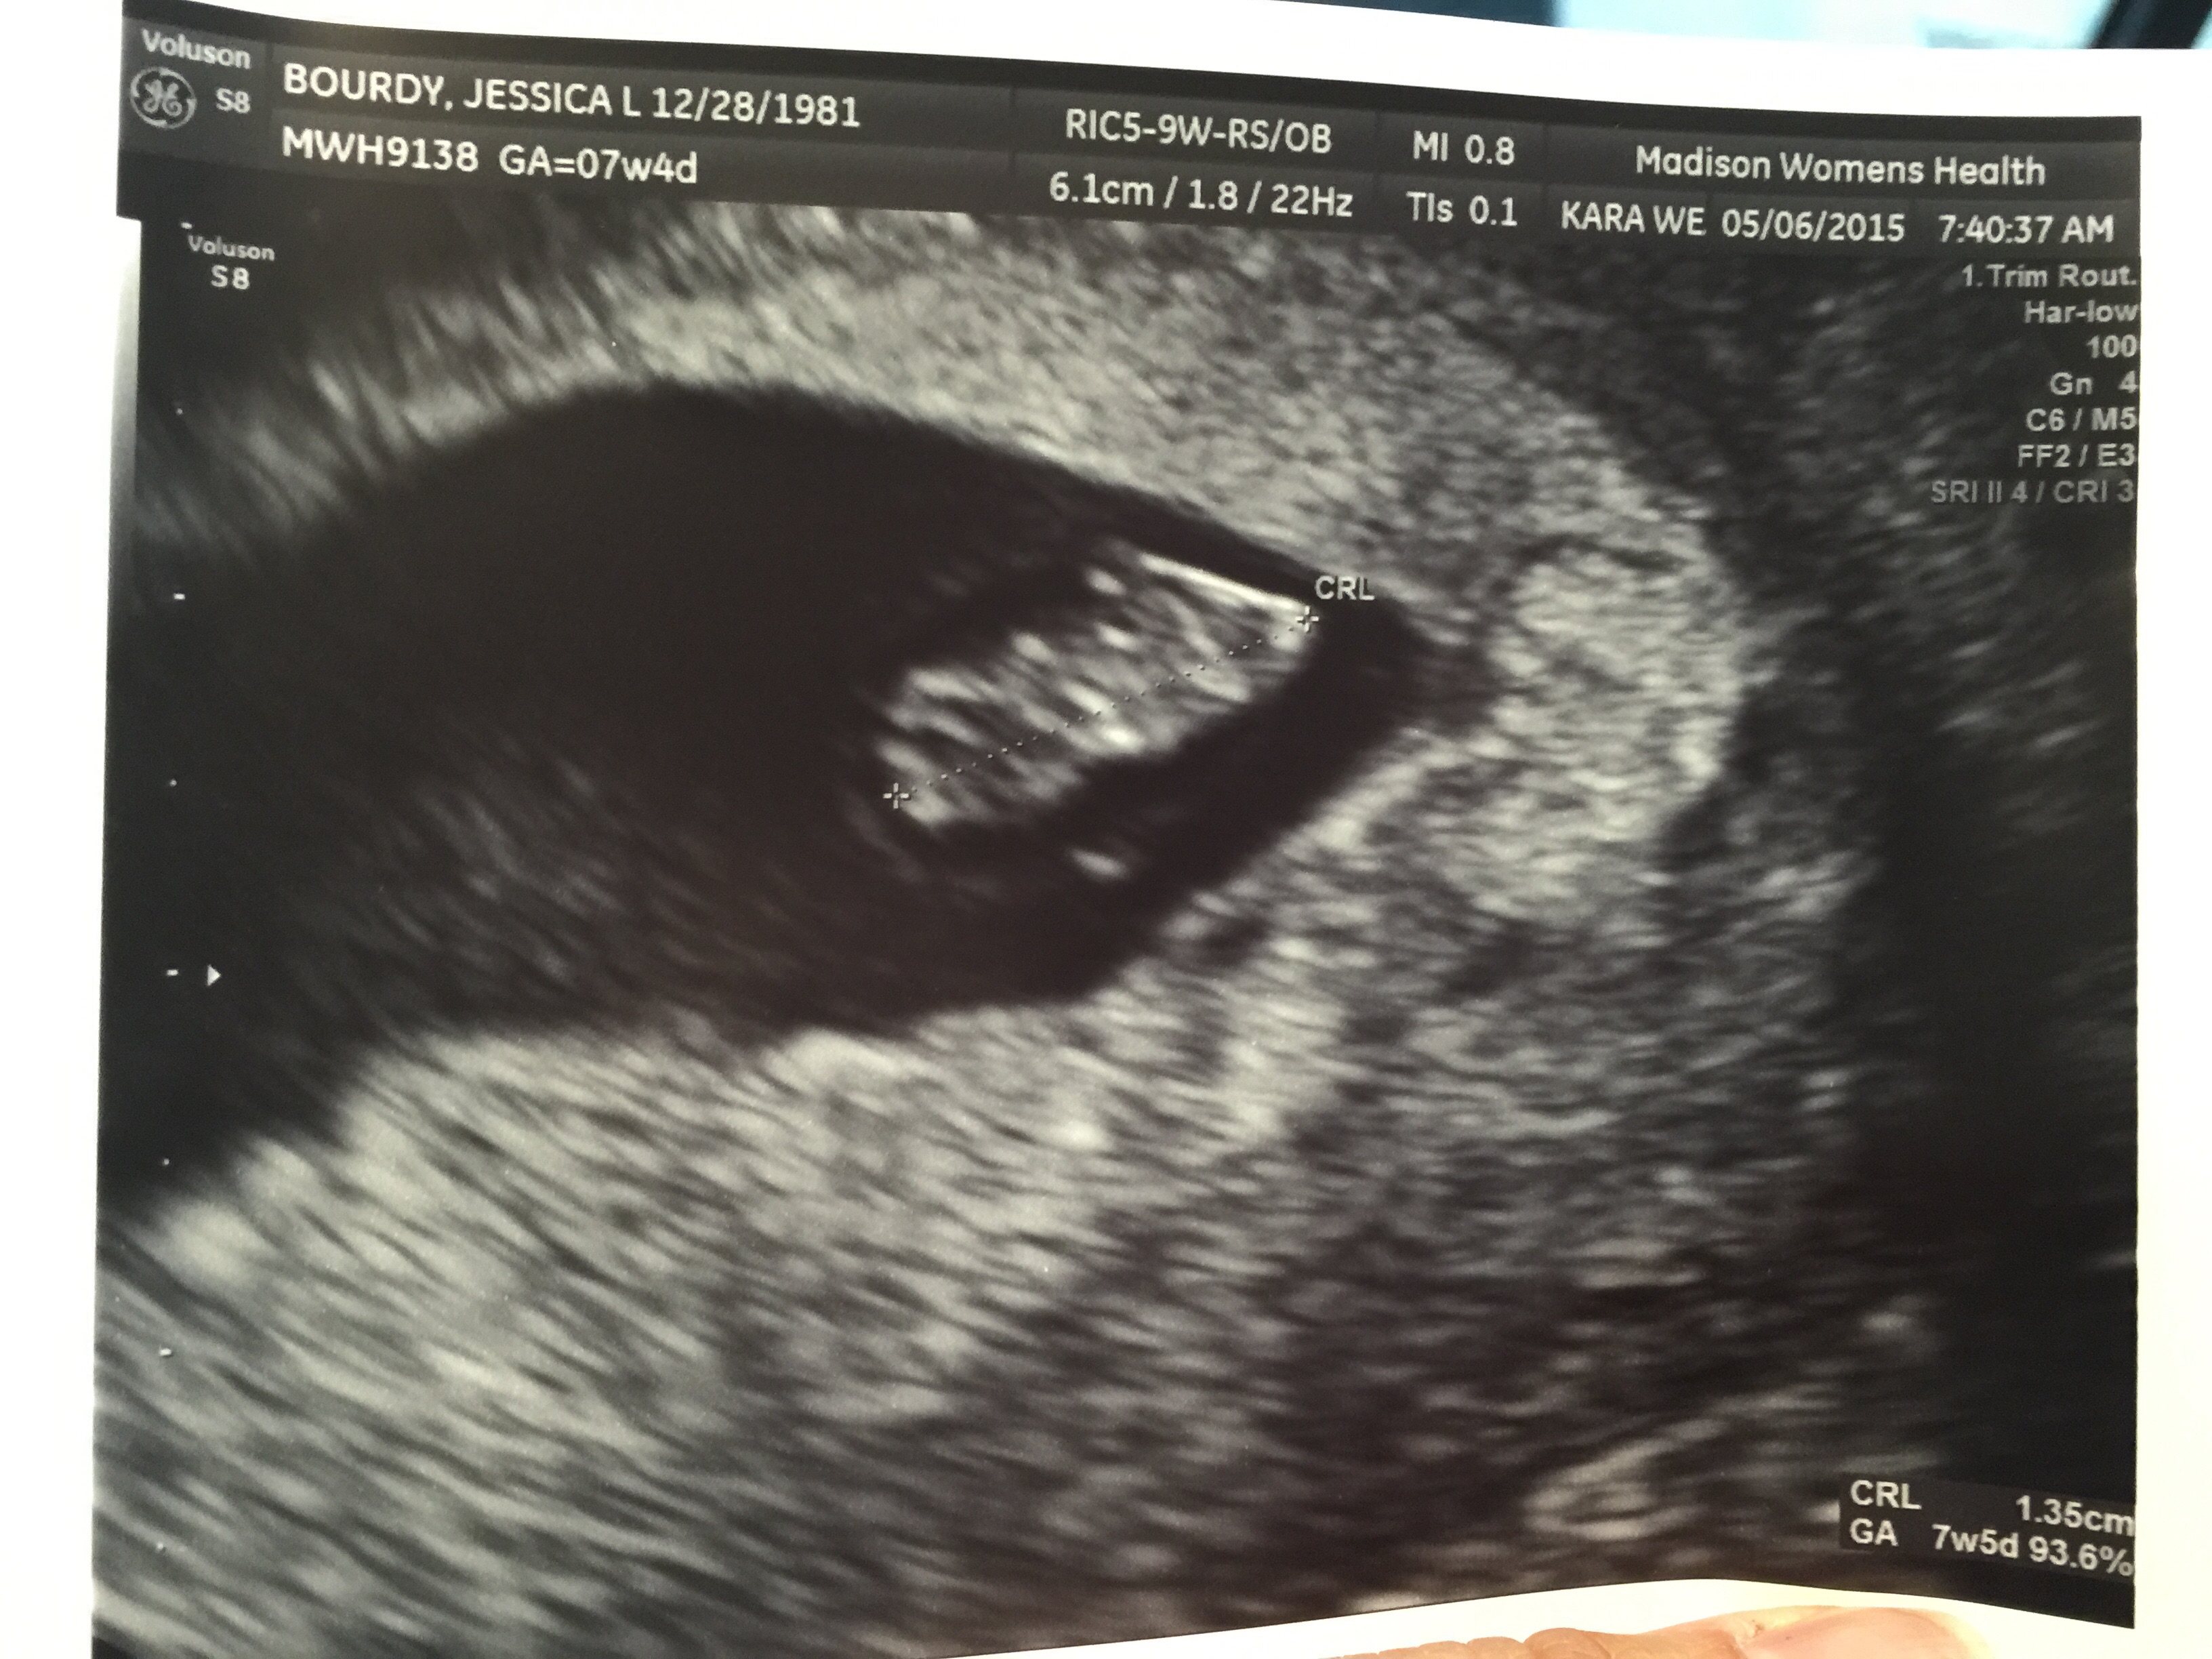

Oh man, this makes me really excited/anxious for my ultrasound on Thursday!!! I'll be 7w and its crazy to see the other 7w ultrasounds and how much it already looks like a baby

They had problems with my bladder being too full to the point I had to empty it like 3-4 times. Small bladder problems lol, but this is 7 weeks 3 days, now I'm 9 weeks and 6 days